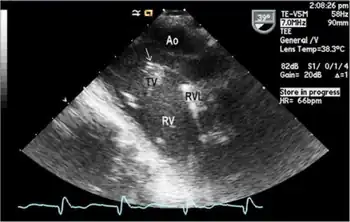

Endocarditis

Presentation

All of these organisms are part of the normal oropharyngeal flora, which grow slowly (up to 14 days), prefer a carbon dioxide–enriched atmosphere, and share an enhanced capacity to produce endocardial infections, especially in young children. Collectively, they account for 5–10% of cases of infective endocarditis involving native valves and are the most common Gram-negative cause of endocarditis among people who do not use drugs intravenously. They have been a frequent cause of culture-negative endocarditis. Culture-negative refers to an inability to produce a colony on regular agar plates because these bacteria are fastidious (require a specific nutrient).